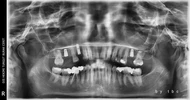

Implant tedavisi